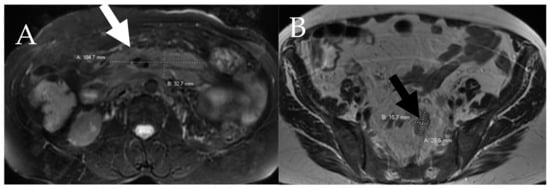

6.1. Skeletal

- Leone, A.; Criscuolo, M.; Gullì, C.; Petrosino, A.; Carlo Bianco, N.; Colosimo, C. Systemic mastocytosis revisited with an emphasis on skeletal manifestations. Radiol. Med. 2021, 126, 585–598. [Google Scholar] [CrossRef] [PubMed]

- Fritz, J.; Fishman, E.K.; Carrino, J.A.; Horger, M.S. Advanced imaging of skeletal manifestations of systemic mastocytosis. Skelet. Radiol. 2012, 41, 887–897. [Google Scholar] [CrossRef] [PubMed]

- Roca, M.; Mota, J.; Giraldo, P.; García Erce, J.A. Systemic mastocytosis: MRI of bone marrow involvement. Eur. Radiol. 1999, 9, 1094–1097. [Google Scholar] [CrossRef]

- Ozturk, K.; Cayci, Z.; Gotlib, J.; Akin, C.; George, T.I.; Ustun, C. Non-hematologic diagnosis of systemic mastocytosis: Collaboration of radiology and pathology. Blood Rev. 2021, 45, 100693. [Google Scholar] [CrossRef]